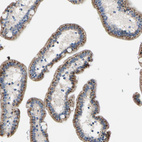

Immunohistochemical staining of human pancreas shows strong cytoplasm granular positivity in exocrine glandular cells.